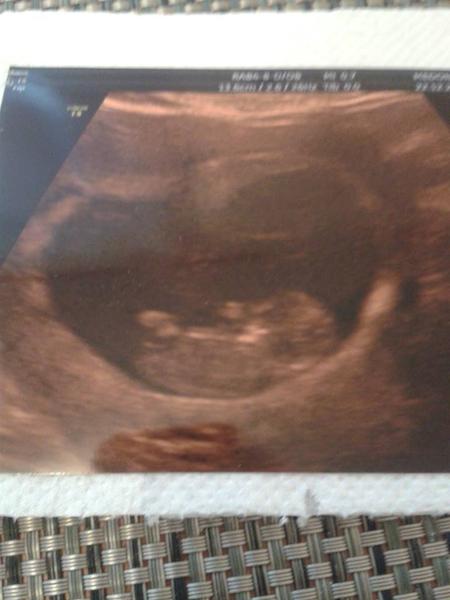

Ked som dorazila, mm ma hned odviezol na pohotovost aby ma vysetrili, a to som tam sla s velmi malou nadejou a dusickou! À le ked mi doki povedal, ze su tam 2, normalne som ani neverila! 😉 A to tu nedavaj vobec ziadne injekcie dokonca nez na SK.... 😒

À le po tyzdni opat kontrola a to uz bolo len jedno bambulko so srdieckom, aspon tak! 🙂